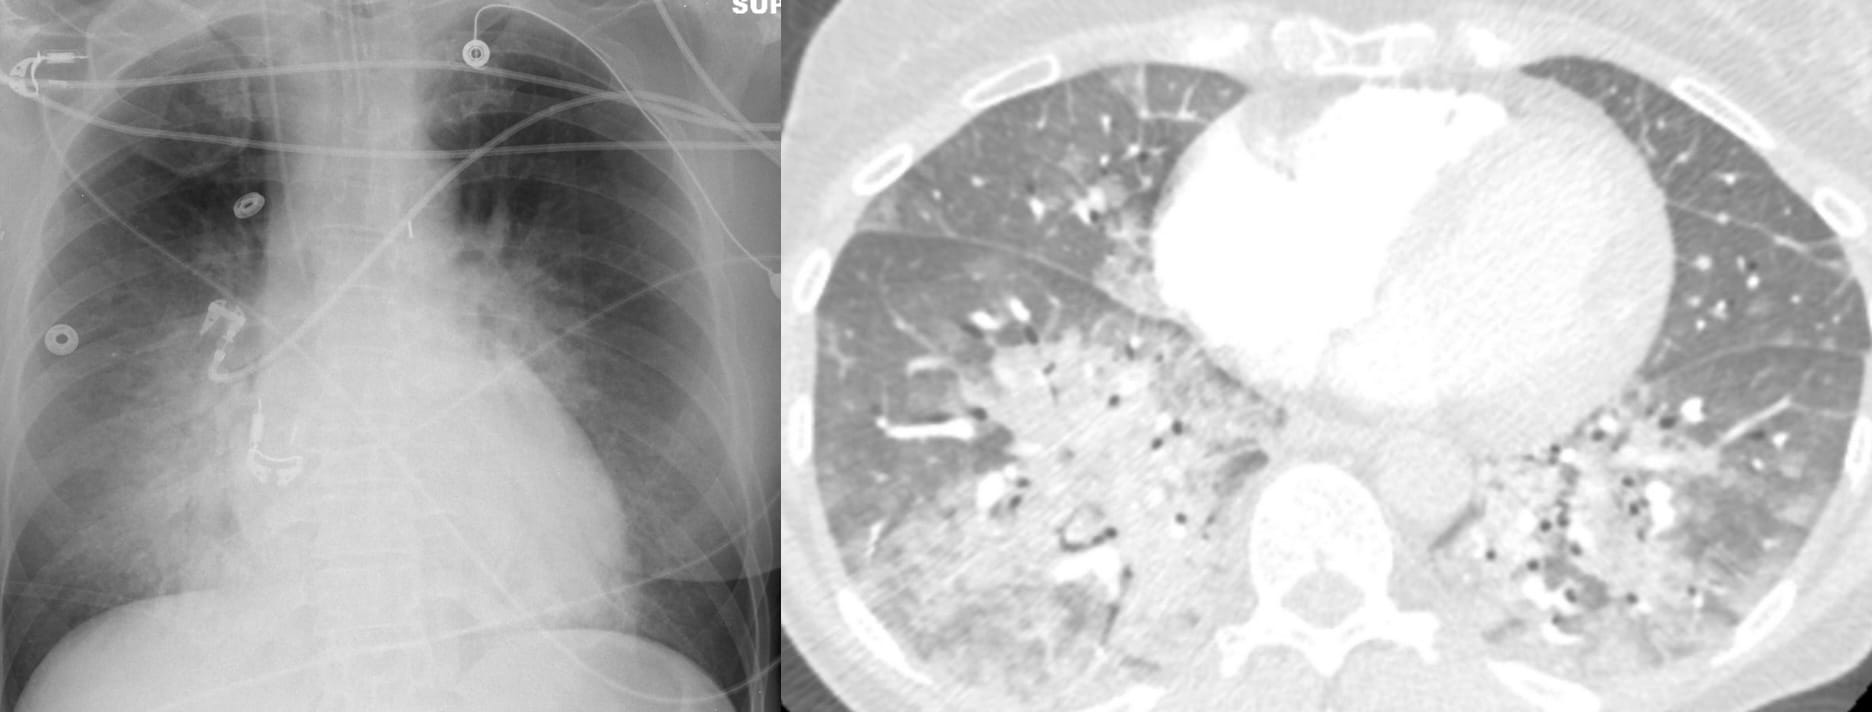

Typical findings in acute lung injury edema

The distribution of edema fluid (consolidation) is typically diffuse and symmetric.

CT of Acute Lung Injury Edema

Don’t confuse the posterior lung opacities with anything else other than consolidated and —particularly—atelectatic lung. This is potentially so-called recruitable (by different ventilatory strategies) lung.